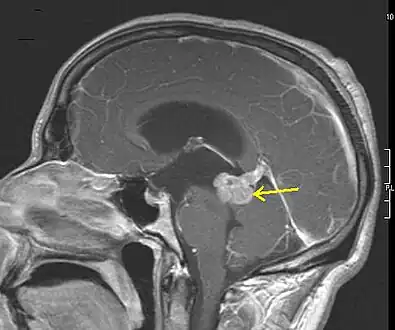

An X-ray computed tomography (CT) or magnetic resonance imaging (MRI) scan is necessary to characterize the extent of these tumors (size, location, consistency). CT will usually show distortion of third and lateral ventricles with displacement of anterior and middle cerebral arteries. Histologic analysis is necessary for grading diagnosis.

In the first stage of diagnosis the doctor will take a history of symptoms and perform a basic neurological exam, including an eye exam and tests of vision, balance, coordination, and mental status. The doctor will then require a CT scan and MRI of the patient's brain. During a CT scan, X-rays of the patient's brain are taken from many different directions. These are then combined by a computer, producing a cross-sectional image of the brain. For an MRI, the patient relaxes in a tunnel-like instrument while the brain is subjected to changes of magnetic field. An image is produced based on the behavior of the brain's water molecules in response to the magnetic fields. A special dye may be injected into a vein before these scans to provide contrast and make tumors easier to identify.